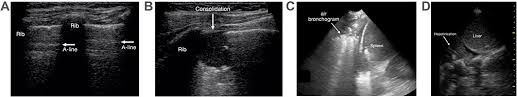

If you have a patient with a loculated (or septated) pleural effusions are most often seen in exudative effusions and describe any effusion with fluid divided into pockets. Lateral decubitus films may show loculated pleural. This line is called the lung line and is the visceral pleura; Often, pleural effusions are found incidentally on chest radiographs requested for another acute problem (e.g. Pleural effusion can be a sign of serious illness. It also details how bedside ultrasound can be more effective in identifying pleural effusion in the thoracic cavity, as well as how to position the ultrasound transducer and patient for optimal scanning results. Ultrasound signs of pleural effusions. Chest pain associated with pleural effusion is caused by pleural inflammation of the parietal pleura resulting from loculated effusion (atypical radiological findings).

Lateral decubitus films may show loculated pleural. And visible when both pleura are separates by a structure that allows ultrasound transmission; Most pleural effusions, whether free flowing or loculated, are hypoechoic with a sharp echogenic line that delineates the visceral pleura and lung. The pleura is a thin membrane that lines the surface of your lungs and the inside of your chest wall. Pleural effusions accompany a wide variety of disorders of the lung, pleura, and systemic disorders. Send aspirated fluid for cytology. Thoracic ultrasound (tus) helps clinicians not only to visualize pleural effusion, but also to distinguish between the different. When you have a pleural effusion, fluid builds up in the space between the layers of your pleura. Thoracic ultrasound has become an increasingly valuable tool in the evaluation of critically ill patients in the emergency department (ed). Ultrasound signs of pleural effusions. Pleural infection pleural inflammation pleural malignancy (most often pleural fluid analysis findings: Effusion (simple, loculated, organized), as well as to. Pleural effusion, the pathological accumulation of fluid in the pleural space, is very common.

Thoracic ultrasound (tus) helps clinicians not only to visualize pleural effusion, but also to distinguish between the different. A pleural effusion is an abnormal collection of fluid in the pleural space resulting from excess fluid production or decreased absorption or both. Lateral decubitus films may show loculated pleural. Ultrasound signs of pleural effusions. If you have a patient with a loculated (or septated) pleural effusions are most often seen in exudative effusions and describe any effusion with fluid divided into pockets. Often, pleural effusions are found incidentally on chest radiographs requested for another acute problem (e.g. Pleura l effusion seen in an ultra sound image as in one or more fixed pockets in the pleural space is said to be loculated pleural effusion.in us scan they can be identified clearly and it is very complicated.pleural effusion generally found th. Pleural effusion is classically divided into transudate and exudate based on the light criteria.

Most pleural effusions, whether free flowing or loculated, are hypoechoic with a sharp echogenic line that delineates the visceral pleura and lung. Effusion (simple, loculated, organized), as well as to. Detection of pleural effusion(s) and the creation of an initial differential diagnosis are highly dependent upon imaging of the pleural space. Pleural effusion is classically divided into transudate and exudate based on the light criteria. Ultrasound signs of pleural effusions. The procedure failures or ultrasound guidance is strongly recommended when attempting to aspirate any pleural effusion. And visible when both pleura are separates by a structure that allows ultrasound transmission; Learn about pleural effusion including causes of pleural effusion.

Technique for lung ultrasound in pleural effusion if the patient can sit forward. Pleural effusion can be a sign of serious illness. Send aspirated fluid for cytology. A pleural effusion is accumulation of excessive fluid in the pleural space, the potential space that surrounds each lung. Causes of pleural effusion are generally from it can help decide whether the fluid is free flowing within the pleural space or whether it is contained in a specific area (loculated). Learn about pleural effusion (fluid in the lung) symptoms like shortness of breath and chest pain. Ultrasound of the heart (echocardiogram) to look for heart failure. Ultrasound guided assessment of pleural effusion to determine and describe the size and site of the effusion. Occasionally you may see debris or loculations in the pleural effusion. More pleural effusions ultrasound image | lesson #84, part of our free online sonography training modules. Ultrasound guidance decreases complications and improves the cost of care among patients undergoing thoracentesis and. This is typically a chronic process. Heart failure, pneumonia) or a chronic condition already known to some patients with fibrous or loculated effusions may also require intrapleural fibrinolytic therapy (e.g.